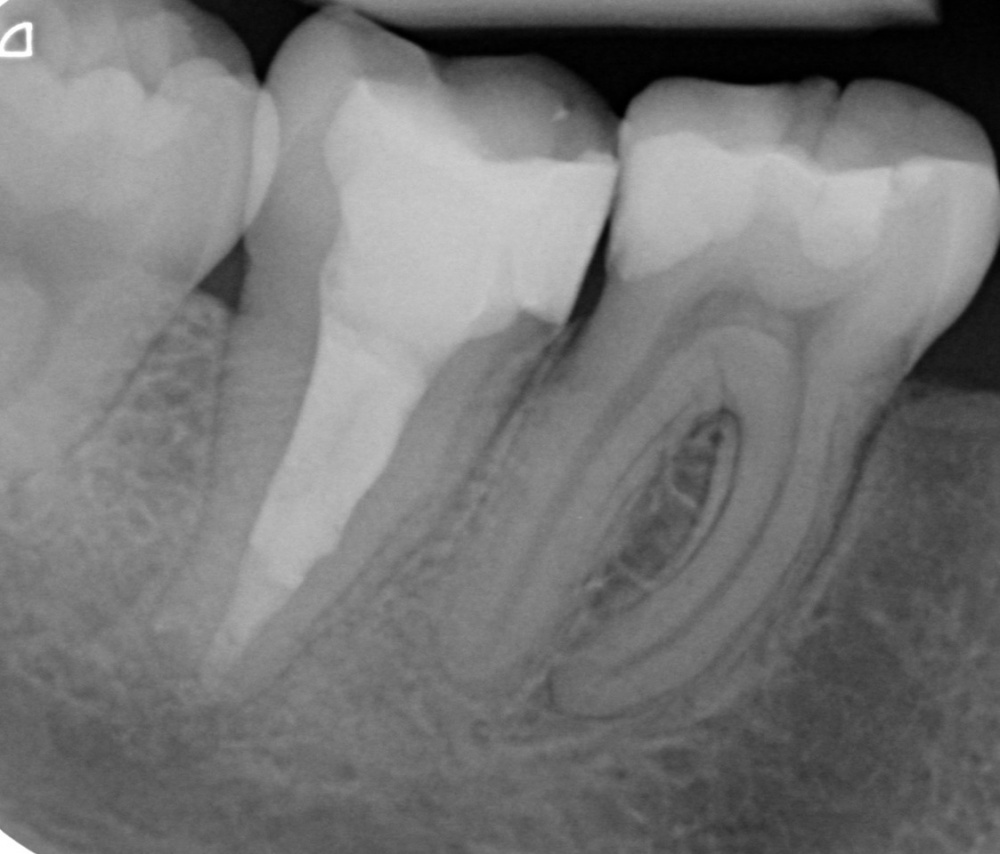

Bei einem folgenden Kontrolltermin war der Patient weiterhin beschwerdefrei, es lag weder eine Schwellung noch ein Lockerungsgrad vor und auch die Perkussionsprobe verlief negativ. Das Kontrollröntgenbild 4 ½ Monate nach Insertion der Wurzelfüllung zeigt eine deutliche Regression der ehemals umfangreichen Osteolyse (Abb. 10). Im weiteren Verlauf der Behandlung ist die Entfernung des Instrumentenfragments aus dem mesiobukkalen Kanals des Zahnes 16 geplant, sowie die anschließende prothetische Neuversorgung der Zähne 16 und 17.